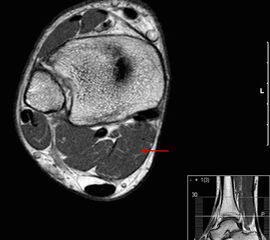

MR-tomographische Darstellung eines unspezifischen weichteiligen Raumforderug im Bereich des dorso-lateralen Rückfußes. Die offene Probebiopsie ergab schließlich die Diagnose eines hochmalignen Synovialsarkoms.

Abbildung 34

10% aller Patienten mit Weichteilsarkomen weisen bei Erst­diagnose bereits Metastasen auf, meist in der Lunge. Drei Viertel der Weichteilsarkome zeigen eine schlechte histo­logische Differenzierung („high-grade“, G3 und G4) und die Letalität beträgt insgesamt über 30%. Trotz des vergleichs­weise seltenen Vorkommens (<1% aller Malignome) gilt diesen Entitäten aufgrund der schlechten Prognose erhöhte Aufmerksamkeit. Das Synovialsarkom ist der häufigste maligne Weichteiltumor im Bereich des Fußes und betrifft hier typischerweise Adoleszente und Erwachsene in der 2. bis zur 5.Lebensdekade (Abb. 34). Zwischen Beginn der Symptome und endgültiger Diagnose­stellung vergehen durchschnittlich 21 Monate. Das Synyovialsarkom zeigt einen unspezifischen klinischen Verlauf mit variabler Wachstumsge- schwindigkeit und kann zahlreiche andere Entitäten imitieren 50. Die Gefahr sowohl pulmonaler/hämatogener als auch lymphogener Metastasen ist hoch.